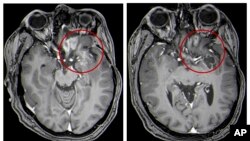

Quiz - Unusual Treatment Shows Promise for Kids With Brain Tumors